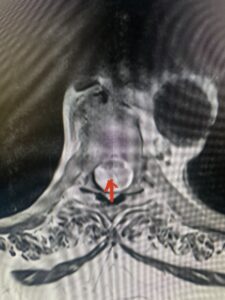

Fig 4. Axial T2-weighted MRIs demonstrating large C5-6 herniated disc with spinal cord compression (red arrow)

Fig 4A. Axial T2 weighted MRIs demonstrating large C5-6 herniated disc with spinal cord compression (red-arrow)

This 36-year-old female who had a long history of neck pain had a history on MRI of a C5-6 bulge. She recently after diving into a pool (not hitting her head on bottom) developed progressive problems with her arms. She had developed spontaneous shocks going down her arms and in the back of her neck. Spontaneous shocks going down the neck and spine is called a Lhermitte’s phenomenon and can occur with spinal cord compression and also with multiple sclerosis. On examination, the patient had long tract weakness of her arms, right greater than left. Her finger extensor weakness was profound on the right. MRI (Fig. 4) of the cervical spine revealed a massive C5-6-disc herniation causing significant cord compression right greater than left with subtle cord signal change. Because of the severe myelopathy, the patient was indicated for surgery. A C5-6 anterior cervical discectomy and fusion was performed (Fig. 5). The patient had a dramatic improvement of her strength in the recovery room.